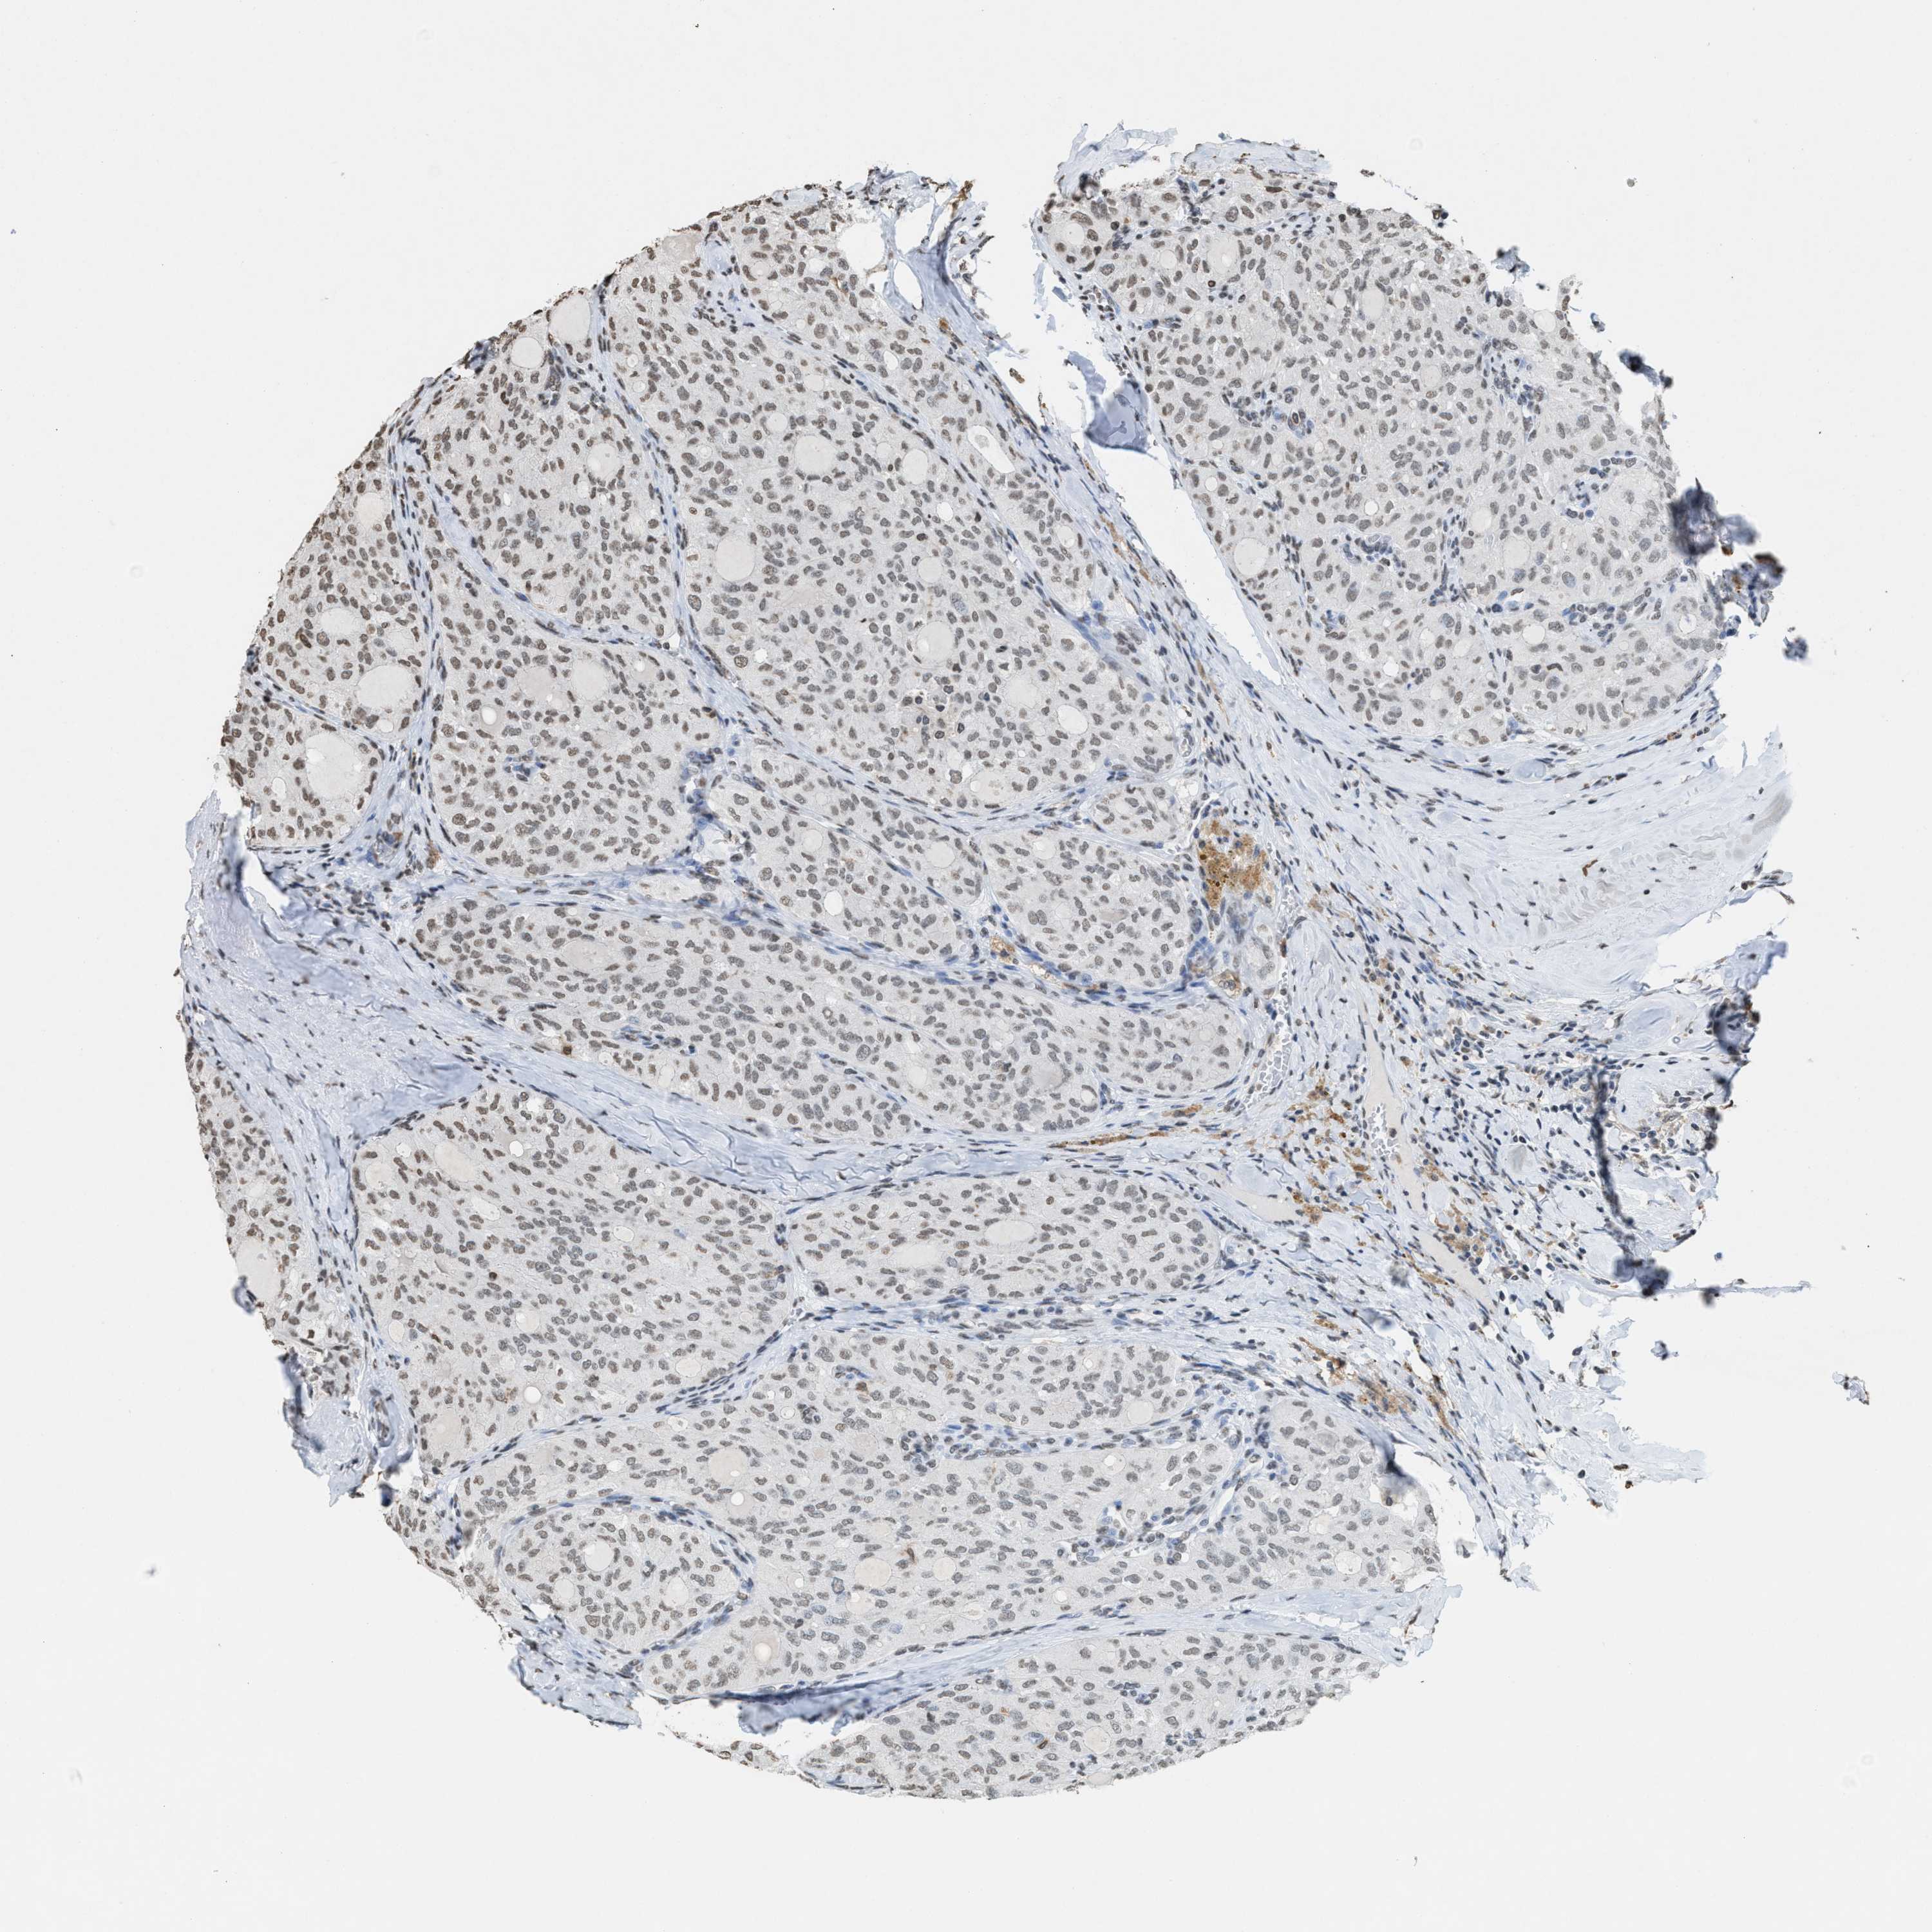

THYROID CANCER - Protein expressioni

A mouse-over function shows sample information and annotation data. Click on an image to view it in a full screen mode. Samples can be filtered based on level of antibody staining by selecting one or several of the following categories: high, medium, low and not detected. The assay and annotation is described here.

Note that samples used for immunohistochemistry by the Human Protein Atlas do not correspond to samples in the TCGA dataset.

Antibody stainingi

Antibody staining in the annotated cell types in the current human tissue is reported as not detected, low, medium, or high, based on conventional immunohistochemistry profiling in selected tissues. This score is based on the combination of the staining intensity and fraction of stained cells.

Each image is clickable and will lead to virtual microscopy that enables deeper exploration of all samples and also displays staining intensity scores, fraction scores and subcellular localization as well as patient and tissue information for each sample.

Antibody HPA021816

Antibody CAB002209

Staining

High

Medium

Low

Not detected

Intensity

Strong

Moderate

Weak

Negative

Quantity

>75%

75%-25%

<25%

None

Location

Nuclear

Cytoplasmic/membranous

Cytoplasmic/membranous,nuclear

Papillary adenocarcinoma, NOS

Follicular adenoma carcinoma, NOS

Carcinoma, NOS